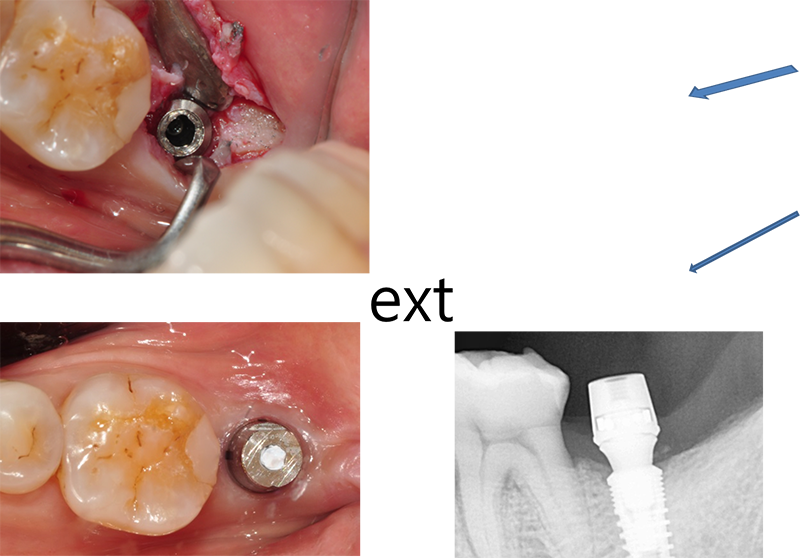

±¸Ä¡ºÎ´Â ½É¹Ìº¸´Ù´Â ÀúÀ۷¸¦ Àß

¹öÅß¾ß ÇÑ´Ù.

Emergence profile¸¦ °Á¶ÇÏÁö ¾Ê´õ¶óµµ

ÀÕ¸öÀÌ ¿ôÀÚ¶ó¼ ÀÚ¿¬½º·´°Ô µÉ ¶§µµ ¸¹´Ù. ±×·¡¼ Ezc abutment¸¦ ¼±ÅÃÇÒ ¶§ °¡´ÉÇÑ equi-gingiva ÀÌ»óÀ¸·Î ¸ÂÃß´Â °Ô À¯¸®ÇÏ´Ù.

ÇȽºÃĵµ Âõ¾îÁú ¼ö ÀÖ°í, ¾î¹þ¸ÕÆ®µµ ºÎ·¯Áú ¼ö ÀÖ´Ù. ¶ÇÇÑ ³ª»ç Ç®¸²µµ ¸¹ÀÌ ¹ß»ýÇÑ´Ù. ÀÌ·± Ưº°ÇÑ °æ¿ì¿¡µµ EZC¿Í °°Àº convertible abutment°¡ À¯¸®ÇÏ´Ù.